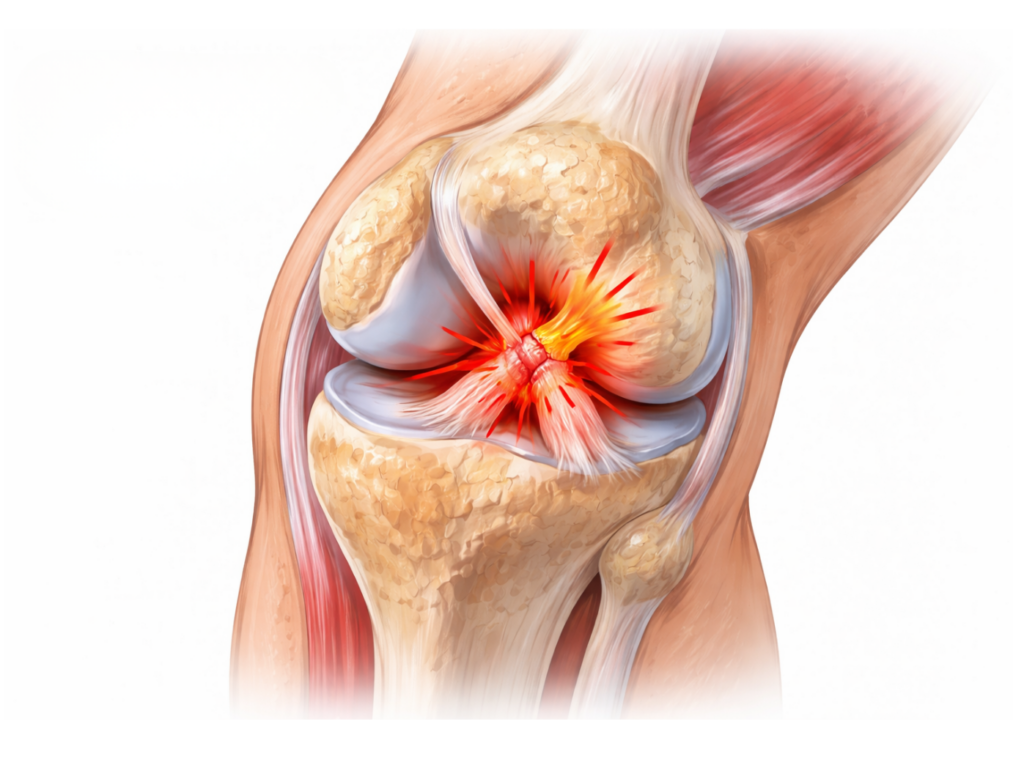

Cos’è, sintomi e cosa fare davvero L’artrosi d’anca, detta anche coxartrosi, è una condizione in cui la cartilagine che riveste l’articolazione dell’anca, si consuma gradualmente. Col tempo possono comparire dolore, rigidità e riduzione della mobilità che influiscono particolarmente su camminata, sonno, lavoro e attività sportive.  Nella maggior parte dei casi, però, esistono strategie efficaci per […]